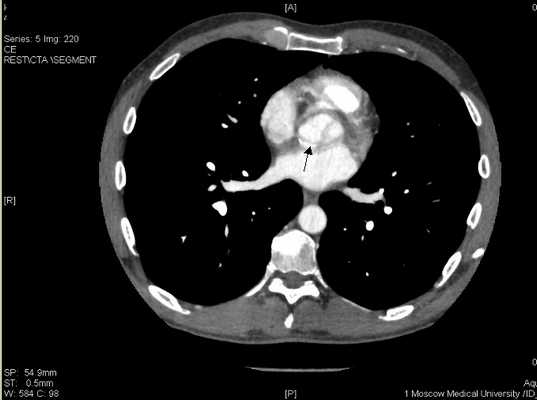

Поскольку от предложенной коронароангиографии пациент вновь отказался, была проведена мультиспиральная компьютерная томография коронарных артерий с контрастированием, которая продемонстрировала протяженный стеноз передней межжелудочковой артерии и окклюзию правой коронарной артерии

Рисунок 11. Стенозирующий атеросклероз коронарных артерий у больного К., 53 лет.

ПМЖВ в проксимальном сегменте имеет кальцинированную протяженную бляшку со стенозированием 50-75% (Указано стрелкой

ПКА в проксимальном сегменте окклюзирована (указано стрелкой), дистальный отдел и ЗМЖВ заполняются контрастным веществом.